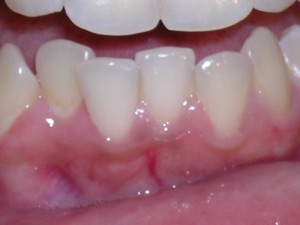

In this case, a young woman came to us with a desire to straighten her teeth. We elected to do Invisalign treatment with some enamel reduction and some dental arch expansion. Take a look...

Here she is on the day of appliance removal. You can see how the crossbite on the right has improved, as well as the lower front teeth crowding. Note that we elected to leave the lower second premolar in it’s rotated form.